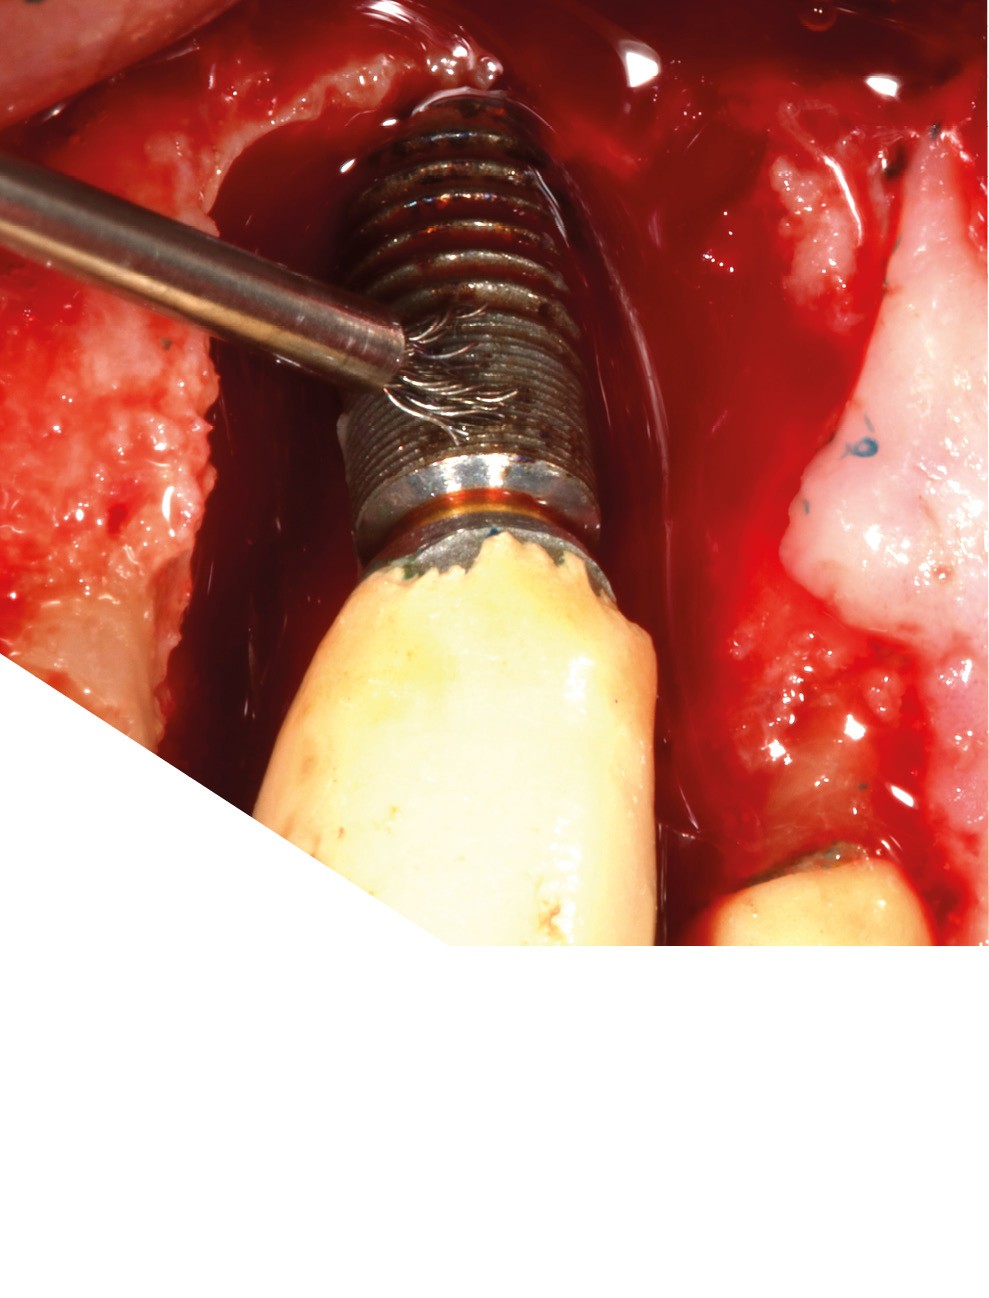

– Le laser Er-YAG, utilisé pour le nettoyage, est un laser avec un milieu actif composé d’yttrium, d’aluminium et de grenat dopé à l’erbium. Avec une longueur d’onde de 2 940 nm situé dans l’infrarouge, le laser Er-YAG est un laser à haute énergie, dont la lumière est absorbée dans l’eau et dans l’hydroxyapatite et qui ne pénètre pas profondément. Ceci permet de couper des tissus mous et des tissus durs, mais également de désorganiser le biofilm bactérie.

C’est un laser idéal pour le traitement chirurgical des péri-implantites. Il permet l’élimination du tissu de granulation à la surface de l’implant et de l’os ainsi qu’une décontamination mécanique par effet photoablatif.– Le laser Diode, utilisé pour la décontamination…